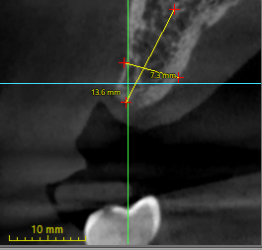

Hi all, Im trying to place a single unit #13. Due to boneloss, it looks like the buccal side is longer than the palatal side. If I were to place #13 completely submerged, 1mm subcrestal on the lingual side, it looks like it would be 2.2mm subcrestal on the buccal side. Should I shave down 1mm of the buccal bone to make it more even?

If so, do…